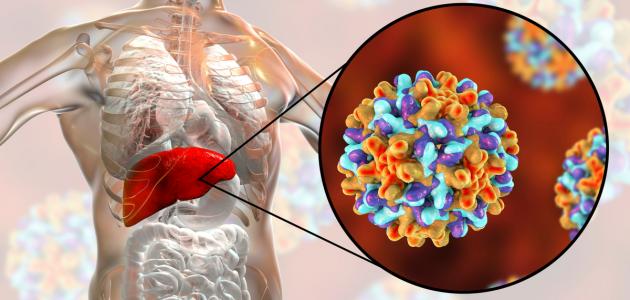

فيروس الكبد ب، أو التهاب الكبد الوبائي ب، أو التهاب الكبد الفيروسي ب، أو مرض الوباء الكبدي ب، أو مرض الكبد الوبائيّ ب (بالإنجليزية: Hepatitis B)، جميعُها مصطلحات تُشير إلى تضرر الكبد والتهابه الناجم عن الإصابة بعدوى فيروسية من نوع فيروس الكبد الوبائي “ب”، ومن الجدير ذكره أنّ هذه العدوى قد تكون حادّة أو مزمنة، وإنّ الالتهاب يتمثّل بانتفاخ أنسجة الجسم المُتأثرة بالإصابة أو العدوى، وقد يترتب على ذلك الإضرار بأعضاء جسم الإنسان، ومن الجدير ذكره أنّ الفيروسات قد تنتقل من شخصٍ لآخر بحيث تغزو خلايا الجسم الطبيعية، وحول طُرق انتقال فيروس الكبد الوبائي “ب” فإنّها تتمّ عن طريق الاتصال مع سوائل جسم مُصاب بهذا الفيروس؛ بما يتضمّن الدم أو السّائل المنوي أو أيّ سوائل أخرى، ويُمكن تحقيق الوقاية من خلال تجنّب العوامل التي من شأنها نقل العدوى إضافةً إلى تلقي المطاعيم الآمنة والفعّالة في الحماية من هذه العدوى، وتبعًا لإحصائيات منظمة الصحة العالمية (بالإنجليزية: World Health Organization) عام 2015م فإنّ المُصابين بالتهاب الكبد الوبائي “ب” المُزمن ممّن يُظهرون نتائجًا إيجابيّة لاختبار مولدات الضد السطحية لفيروس التهاب الكبد (ب) (بالإنجليزية: Hepatitis B Surface Antigen) واختصارًا (HBsAg) يبلغ عددهم حوالي 257 مليون مُصاب، ووفقًا لإحصائيّاتها عام 2016م فإنّ ما يُقارب 27 مليونًا من المُصابين بهذه العدوى يُدركون إصابتهم بها، في حين يبلغ عدد الخاضعين للعلاج 4.5 مليون مُصاب ممّن تمّ تشخيصهم بهذه الحالة.[١][٢]

كما تمّت الإشارة سابقًا فإنّ التهاب الكبد الوبائي “ب” يُعزى إلى العدوى بفيروس الكبد الوبائي “ب”، وقد تظهر بعض الأعراض على المُصابين بهذا المرض دون أن يُدرِكوا إصابتهم بهذه العدوى، وعليه فإنّه ذلك قد يتسبّب بنقل العدوى للآخرين دون معرفتهم بذلك، وإنّ عدم إجراء التدخلات الفورية والفعّالة قد يتسبّب بزيادة عدد المُصابين بالعدوى، وتنتشر هذه العدوى في بعض مناطق العالم وتكون شائعة في مناطق مُعينة أكثر من غيرها، ويُشار إلى اختلاف النمط الجيني للفيروس المُنتشر أيضًا من بلدٍ لآخر، إذ يُعتبر النمط الجيني “أ” لفيروس الكبد الوبائي “ب” هو الأكثر انتشارًا في الولايات المُتحدة الأمريكية، بينما يُعدّ النمط الجيني “د” هو السّائد في مناطق الشرق الأوسط ومعظم دول أوروبا، ويُمكن تصنيف المناطق الجغرافية بناءً على شدّة العدوى إلى شديدة العدوى أو متوسطة العدوى،[٤] [٥] وفيما يأتي بيان لأبرز مناطق العالم التي تنتشر فيها العدوى بهذا الفيروس:[٦]